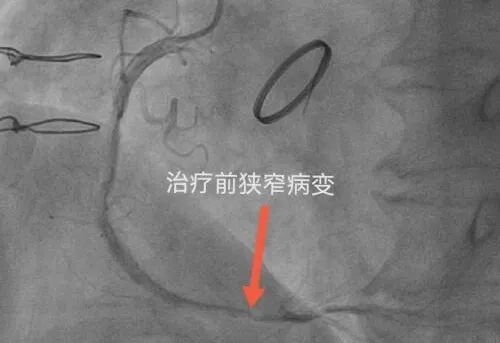

杨大爷今年76岁,罹患高血压病、糖尿病多年,1993年因主动脉瓣关闭不全行主动脉瓣机械瓣置换术,术后长期口服抗凝药物预防血栓;2016年,诊断出冠心病并于右冠状动脉植入了支架;2019年发现心房颤动、频发室性早搏;2023年12月,患者再发胸痛气短等症状,就诊于当地医院通过冠脉造影诊断冠脉三支病变,病变弥漫狭窄并伴有迂曲钙化,威胁着患者的生命安全,该院医生认为行介入手术难度高,且因患者服用抗凝药物,所以手术及术后风险极大,建议患者采用外科搭桥手术治疗。但杨大爷年龄较高,身体状况一般且基础疾病多,心功能差等情况让患者及家属对二次开胸手术望而却步。

1月8日,心病科团队经过前期的周密准备,为杨大爷制定了详细的手术方案。当天,李爱勇主任及其介入团队为患者顺利实施了冠脉介入手术,成功进行了药物球囊扩张术,开通了杨大爷心脏堵塞的血管,为杨大爷带来了重获新生的希望。整个手术过程持续了2个多小时,手术一开始因患者右侧桡动脉明显迂曲给穿刺带来了极大的困难,但李主任考虑患者之前股动脉造影时不良后果明显,经过耐心尝试最终顺利完成桡动脉穿刺达到造影指定位置,之后手术进行顺利,杨大爷全程意识清晰,术后杨大爷胸闷气短等症状明显缓解,目前恢复良好。